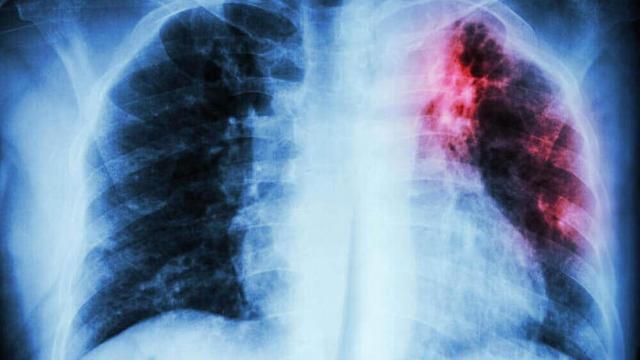

Cáncer de páncreas